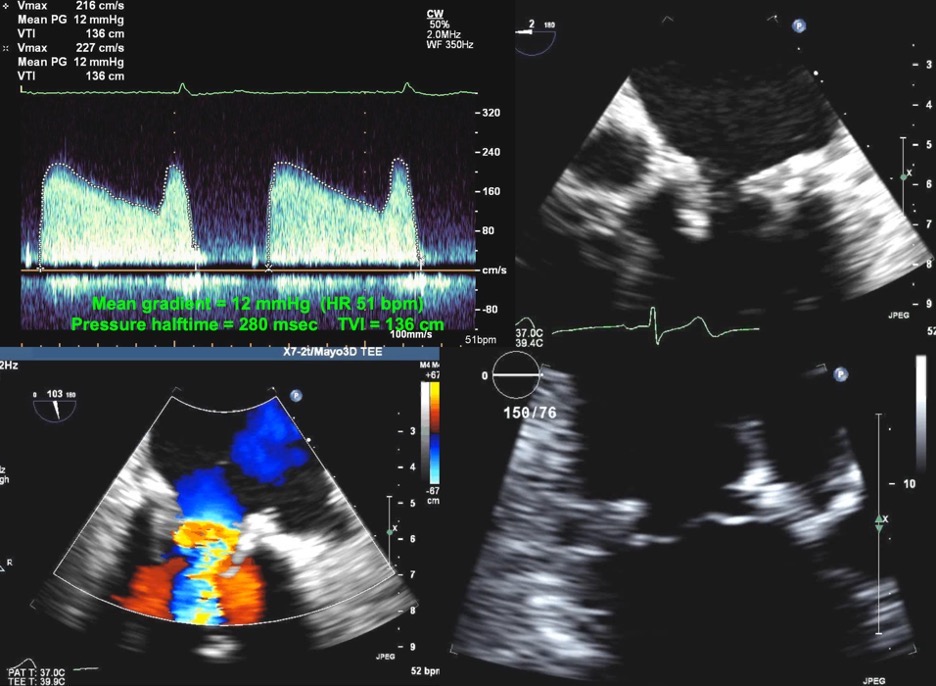

Fig. 7.Echocardiographic imaging of a patient with a mitral bioprosthesis and heart failure symptoms found to have prosthetic thrombosis.

Top Left: Continuous Wave Doppler in a patient with a

31 mm Hancock porcine mitral bioprosthesis who presented with dyspnea on exertion

and lightheadedness. The mean gradient was 12 mmHg with a heart rate of 51 and a

pressure halftime of 280 msec. The DVI was 5.7, with an EOAi of 0.44

cm